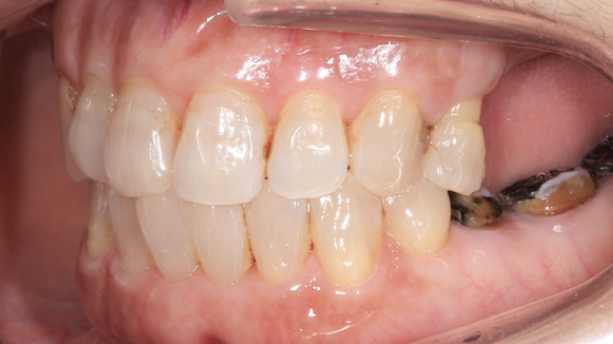

外れた左下の歯ですが、歯茎から出ている歯の部分が明らかに短く、この状態で被せ直しをしても維持力がないためすぐに外れてしまう事が予想されました。

また、奥歯がないためこの歯には噛む時の力が過剰にかかってしまいます。

この方の場合右の歯も少なく、主訴である左下の歯だけ治療をしたとしても今残っている歯も含めてどんどん悪くなることが予想されました。

このような理由で口腔全体を含めた「全顎の治療」計画を提案させていただきました。

現状残っている歯の状態から、この患者さまは「生理的咬合」であると診断し、現状噛んでいる歯の位置の修正とは行わずに、歯がないところ、歯が欠けているところを治すだけで安定すると考え治療を行っています。

この歯(黄色の印)は顎を横に動かした時に強い力が加わり、歯の周囲の組織にダメージが出ているため、力をコントロールするために歯の形を修正が必要です。

右の奥歯についても歯が伸びてしまっているのでこちらは部分的な矯正治療と歯茎の手術で対応しています。